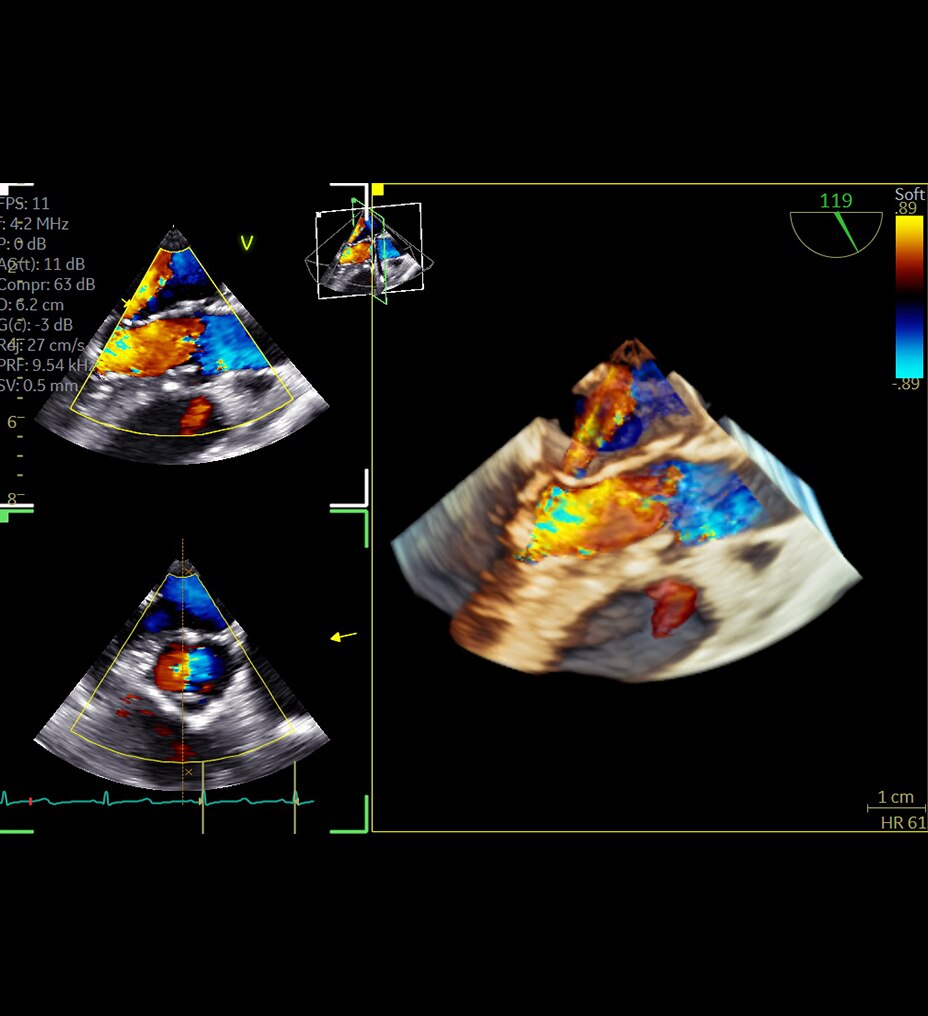

В видеоролике представлен практический опыт внедрения технологии Air Recon DL (ARDL) — технологии реконструкции МР-изображений на основе алгоритмов глубокого обучения. В отличие от традиционных методов постобработки ARDL позволяет значительно снизить уровень шума, повысить пространственное разрешение и четкость изображений без увеличения времени сканирования.

Специалисты клиник "СМТ" рассказывают о влиянии ARDL на ключевые аспекты медицинской деятельности: качество диагностики, эффективность рабочих процессов и комфорт пациентов.